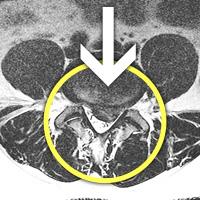

MRI